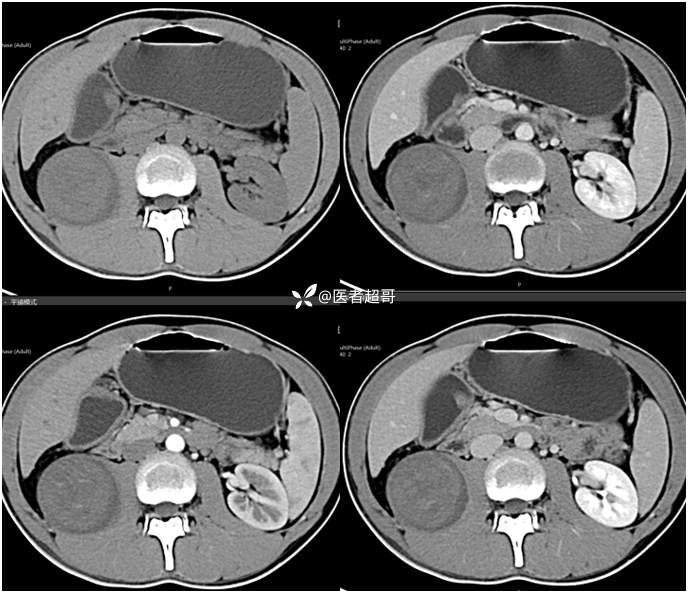

【影诊笔记754】腰痛就诊,腹膜后实性占位,请诊断分析!

主 诉:腰痛2月。

现病史:患者2月前无明显诱因出现腰背部疼痛,夜间为著。患者无头痛、头晕,无恶心、呕吐,无胸闷、憋气,无腹痛、腹胀。无尿频、尿急、尿痛等现象。患者在院外未作特殊治疗。为求进一步诊疗,来我院肾内科门诊就诊。门诊行双肾、输尿管、膀胱(前列腺)彩超提示:腹膜后实性占位。患者遂来我科就诊。我科以“腰痛”收治入院,患者自发病以来,神志清,精神可,饮食可,睡眠差。小便如上述,大便未见明显异常。体重无明显增减。